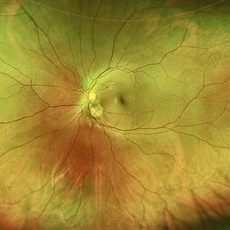

Exudative Retinal Detachment

Exudative Retinal Detachment

Aug 6 2025 by Aditya S Kelkar, MS, FRCS, FASRS,FRCOphth

Fundus auto-fluorescence of a 41 year old female depicting retinal pigment epitheliopathy and exudative retinal detachment in case of ocular metastasis secondary to breast carcinoma.

Photographer: Dr.Rabia Naaz, National Institute of ophthalmology, Pune

Imaging device: OPTOS DAYTONA

Condition/keywords: Exudative retinal detachment, Retinal pigment epitheliopathy